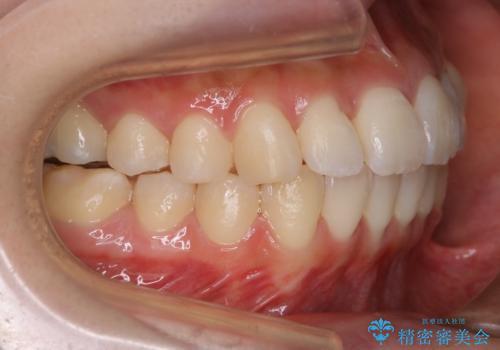

- 上下の歯のガタつきを主訴にご来院されました。

前歯部に特にガタつきが見られ、正中もズレている状態でした。

矯正装置の希望がインビザラインだったため、マイクロインプラントを併用し、奥歯から順に遠心移動をかけていくことにより非抜歯でも主訴のガタつきを治すことができました。

術前・術後の笑った時の歯の見え方の変化にも注目してみてください!